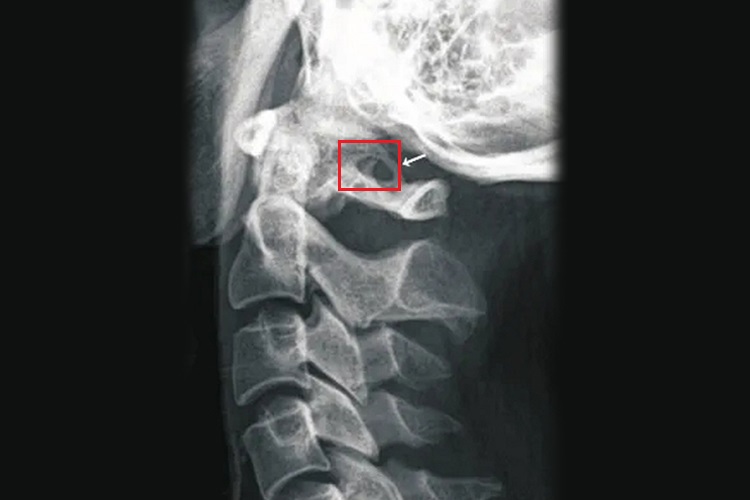

寰椎椎动脉沟环畸形患者会有头晕、猝倒、上颈痛,眼部可出现痛感、视力模糊及疲劳感等,耳部可出现耳鸣、听力下降及耳痛等,其他症状还包括头痛、恶心、厌食及其他颈椎痛症状等。在X线平片侧位上可清晰显示沟环之形态及侧别。